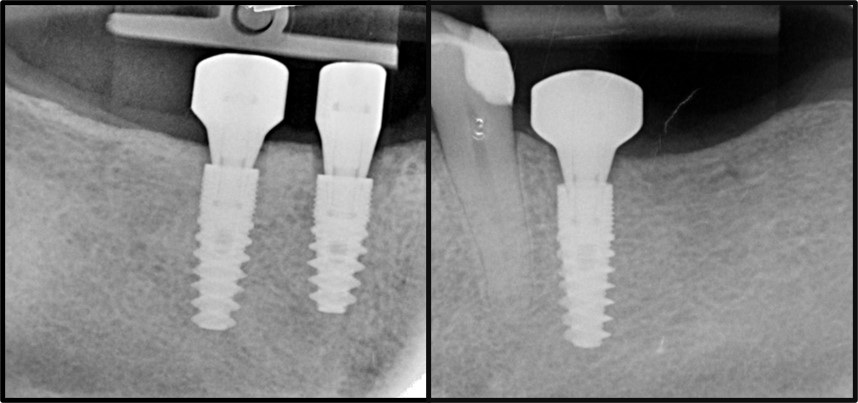

Il controllo radiografico finale evidenziava il buon esito dell’intervento e la riproduzione fedele del progetto digitale iniziale (Figura 8).